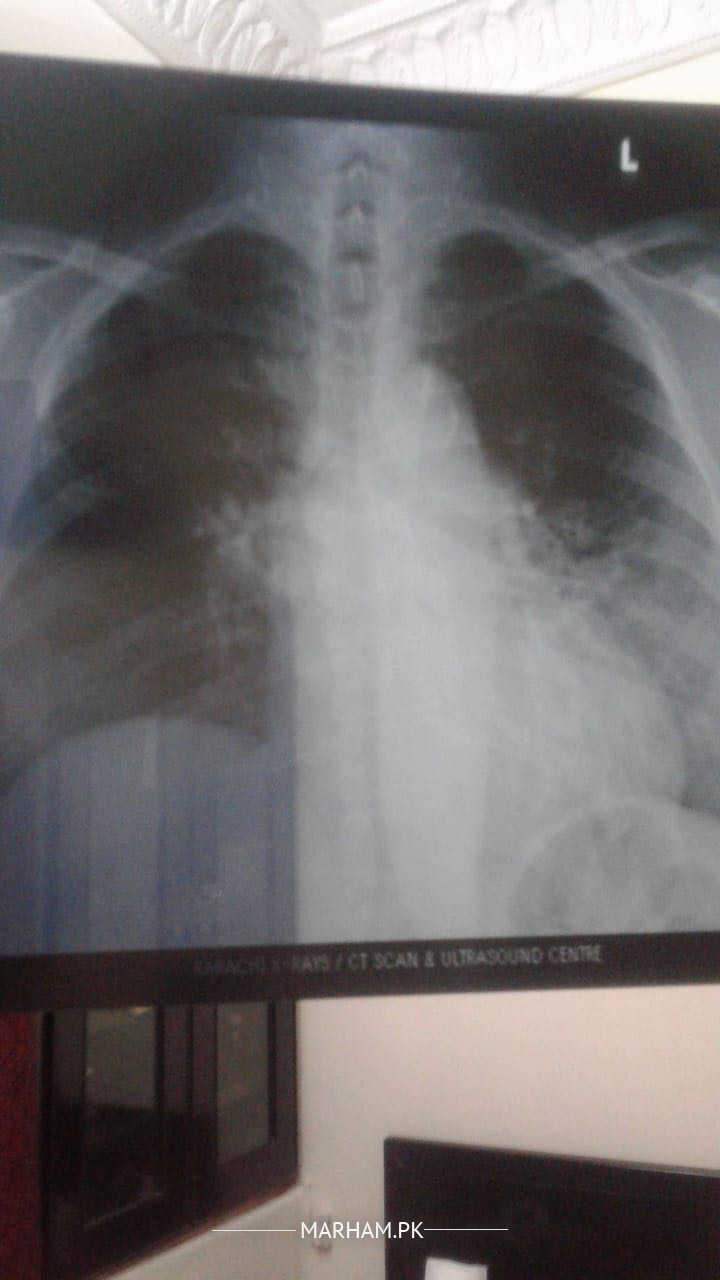

Asking on behalf of my mother she is 54 yrs old. She had a covid in December 2020, it was so severe and treated at home by having instructions from family dr. Now she is still having a cough covid tested again it’s negative. I am attaching her xray report and pictures. If any could suggest some remedies or medicine. Had fever but after taking Panadol currently she doesn’t have a fever. But feeling weakness. Today she started cefiget 400Mg

This her current xray